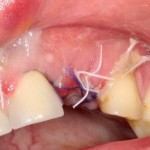

Трансплантация десны, аугментация лунки

Для определения размеров будущего мягкотканного аутотрансплантата мы использовали пародонтологический зонд. С помощью него мы выбрали донорскую зону (бугор верхней челюсти или небная сторона альвеолярного отростка верхней челюсти в области моляров), с помощью скальпеля получили необходимый по размеру аутотрансплантат (мягкотканный лоскут для пересадки).

Затем, мы подготовили ксенографт Bio-Oss Collagen. Обычно на 2 зуба (центральных резца) с избытком хватает 100-миллиграмовой упаковки. Имеющийся в ней параллелепипед мы поделили на 2 усеченные пирамиды с основанием в 2/3 ширины изначального блока.

Если вы когда-нибудь видели подобные операции, то наверняка обращали внимание на порядок действий — сначала устанавливаются имплантаты, затем укладывается графт и только потом фиксируется мягкотканный аутотрансплантат. Для удобства в этом и похожих клинических ситуациях мы поменяли порядок действий:

Сначала мы провели и зафиксировали деэпителизированный соединительнотканный аутотрансплантат (ССТ). Для этого мы сформировали тоннель и использовали ортодонтическую проволоку в качестве проводника. Подробнее об этой методике можно почитать здесь>>.

Затем уложили ксенографт. Особенностями Bio-Oss Collagen являются удобство адаптации, устойчивость к вымыванию и выдавливанию, поэтому мы просто уложили полученные ранее пирамидки вестибулярно относительно будущего имплантата, после чего прижали их с помощью уже упоминавшихся аналогов имплантата, входящих в хирургический набор имплантационной системы Xive (кстати, при работе с другими имплантационными системами для паковки графта в лунке можно использовать круглые остеотомы для синуслифтинга).

В совокупности, аугментация лунок перед установкой имплантатов занимает около 20 минут — и это самый долгий из всех хирургических этапов лечения.